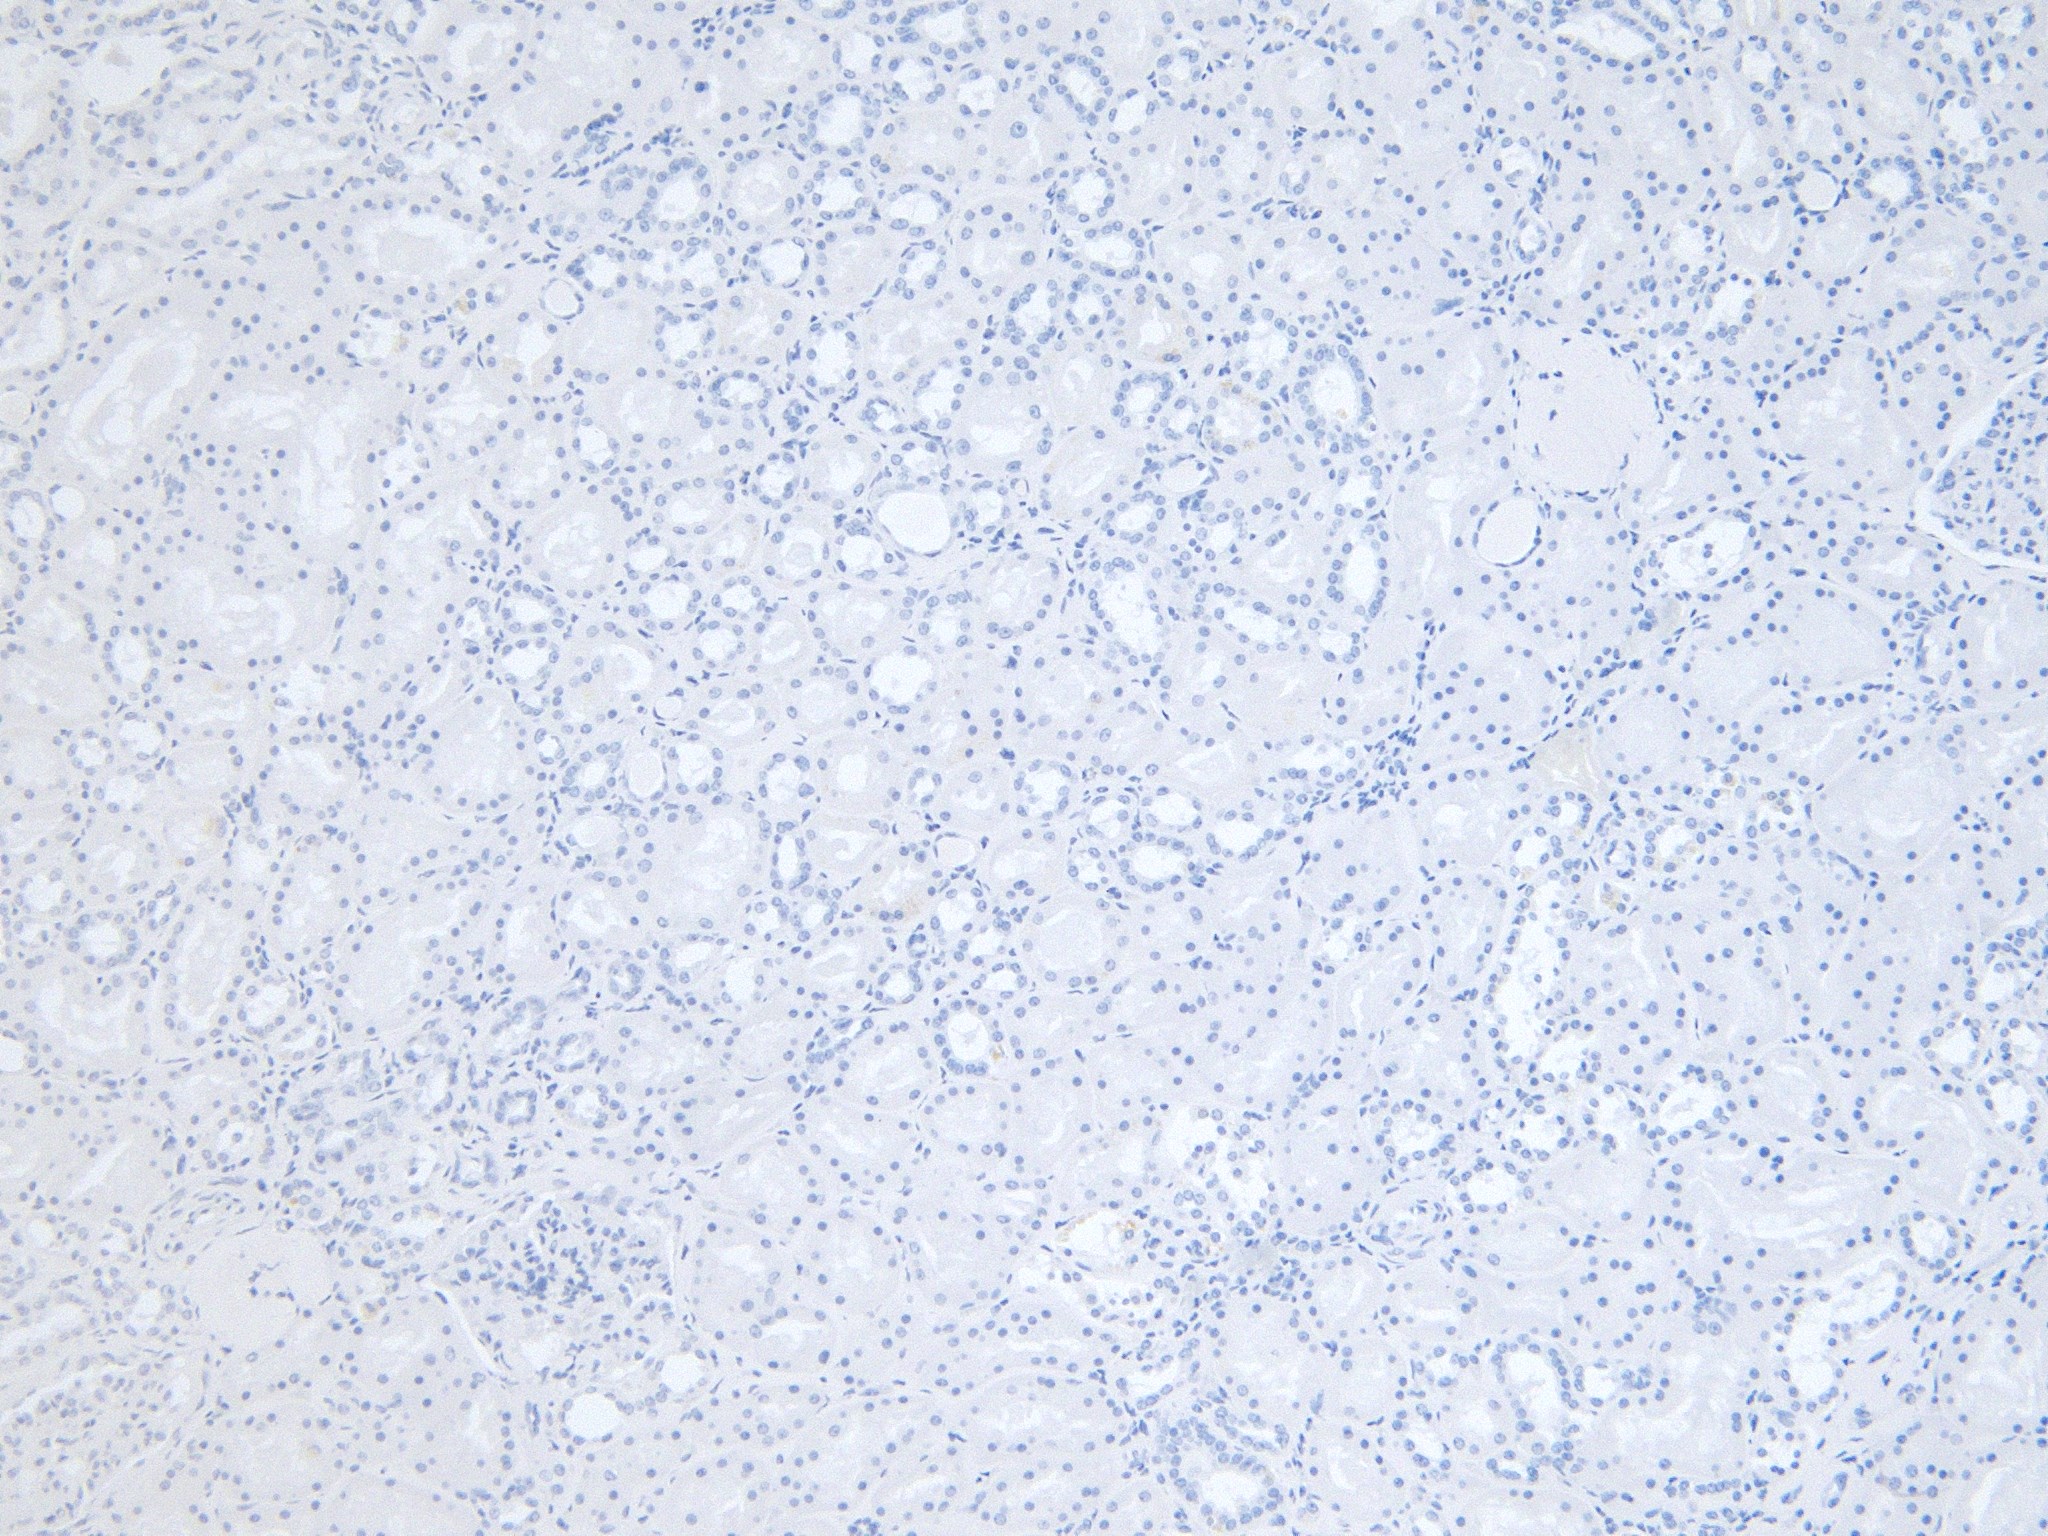

IHC Results Paraffin embedded Human Kidney. Recommended concentration: 5µg/ml. | |